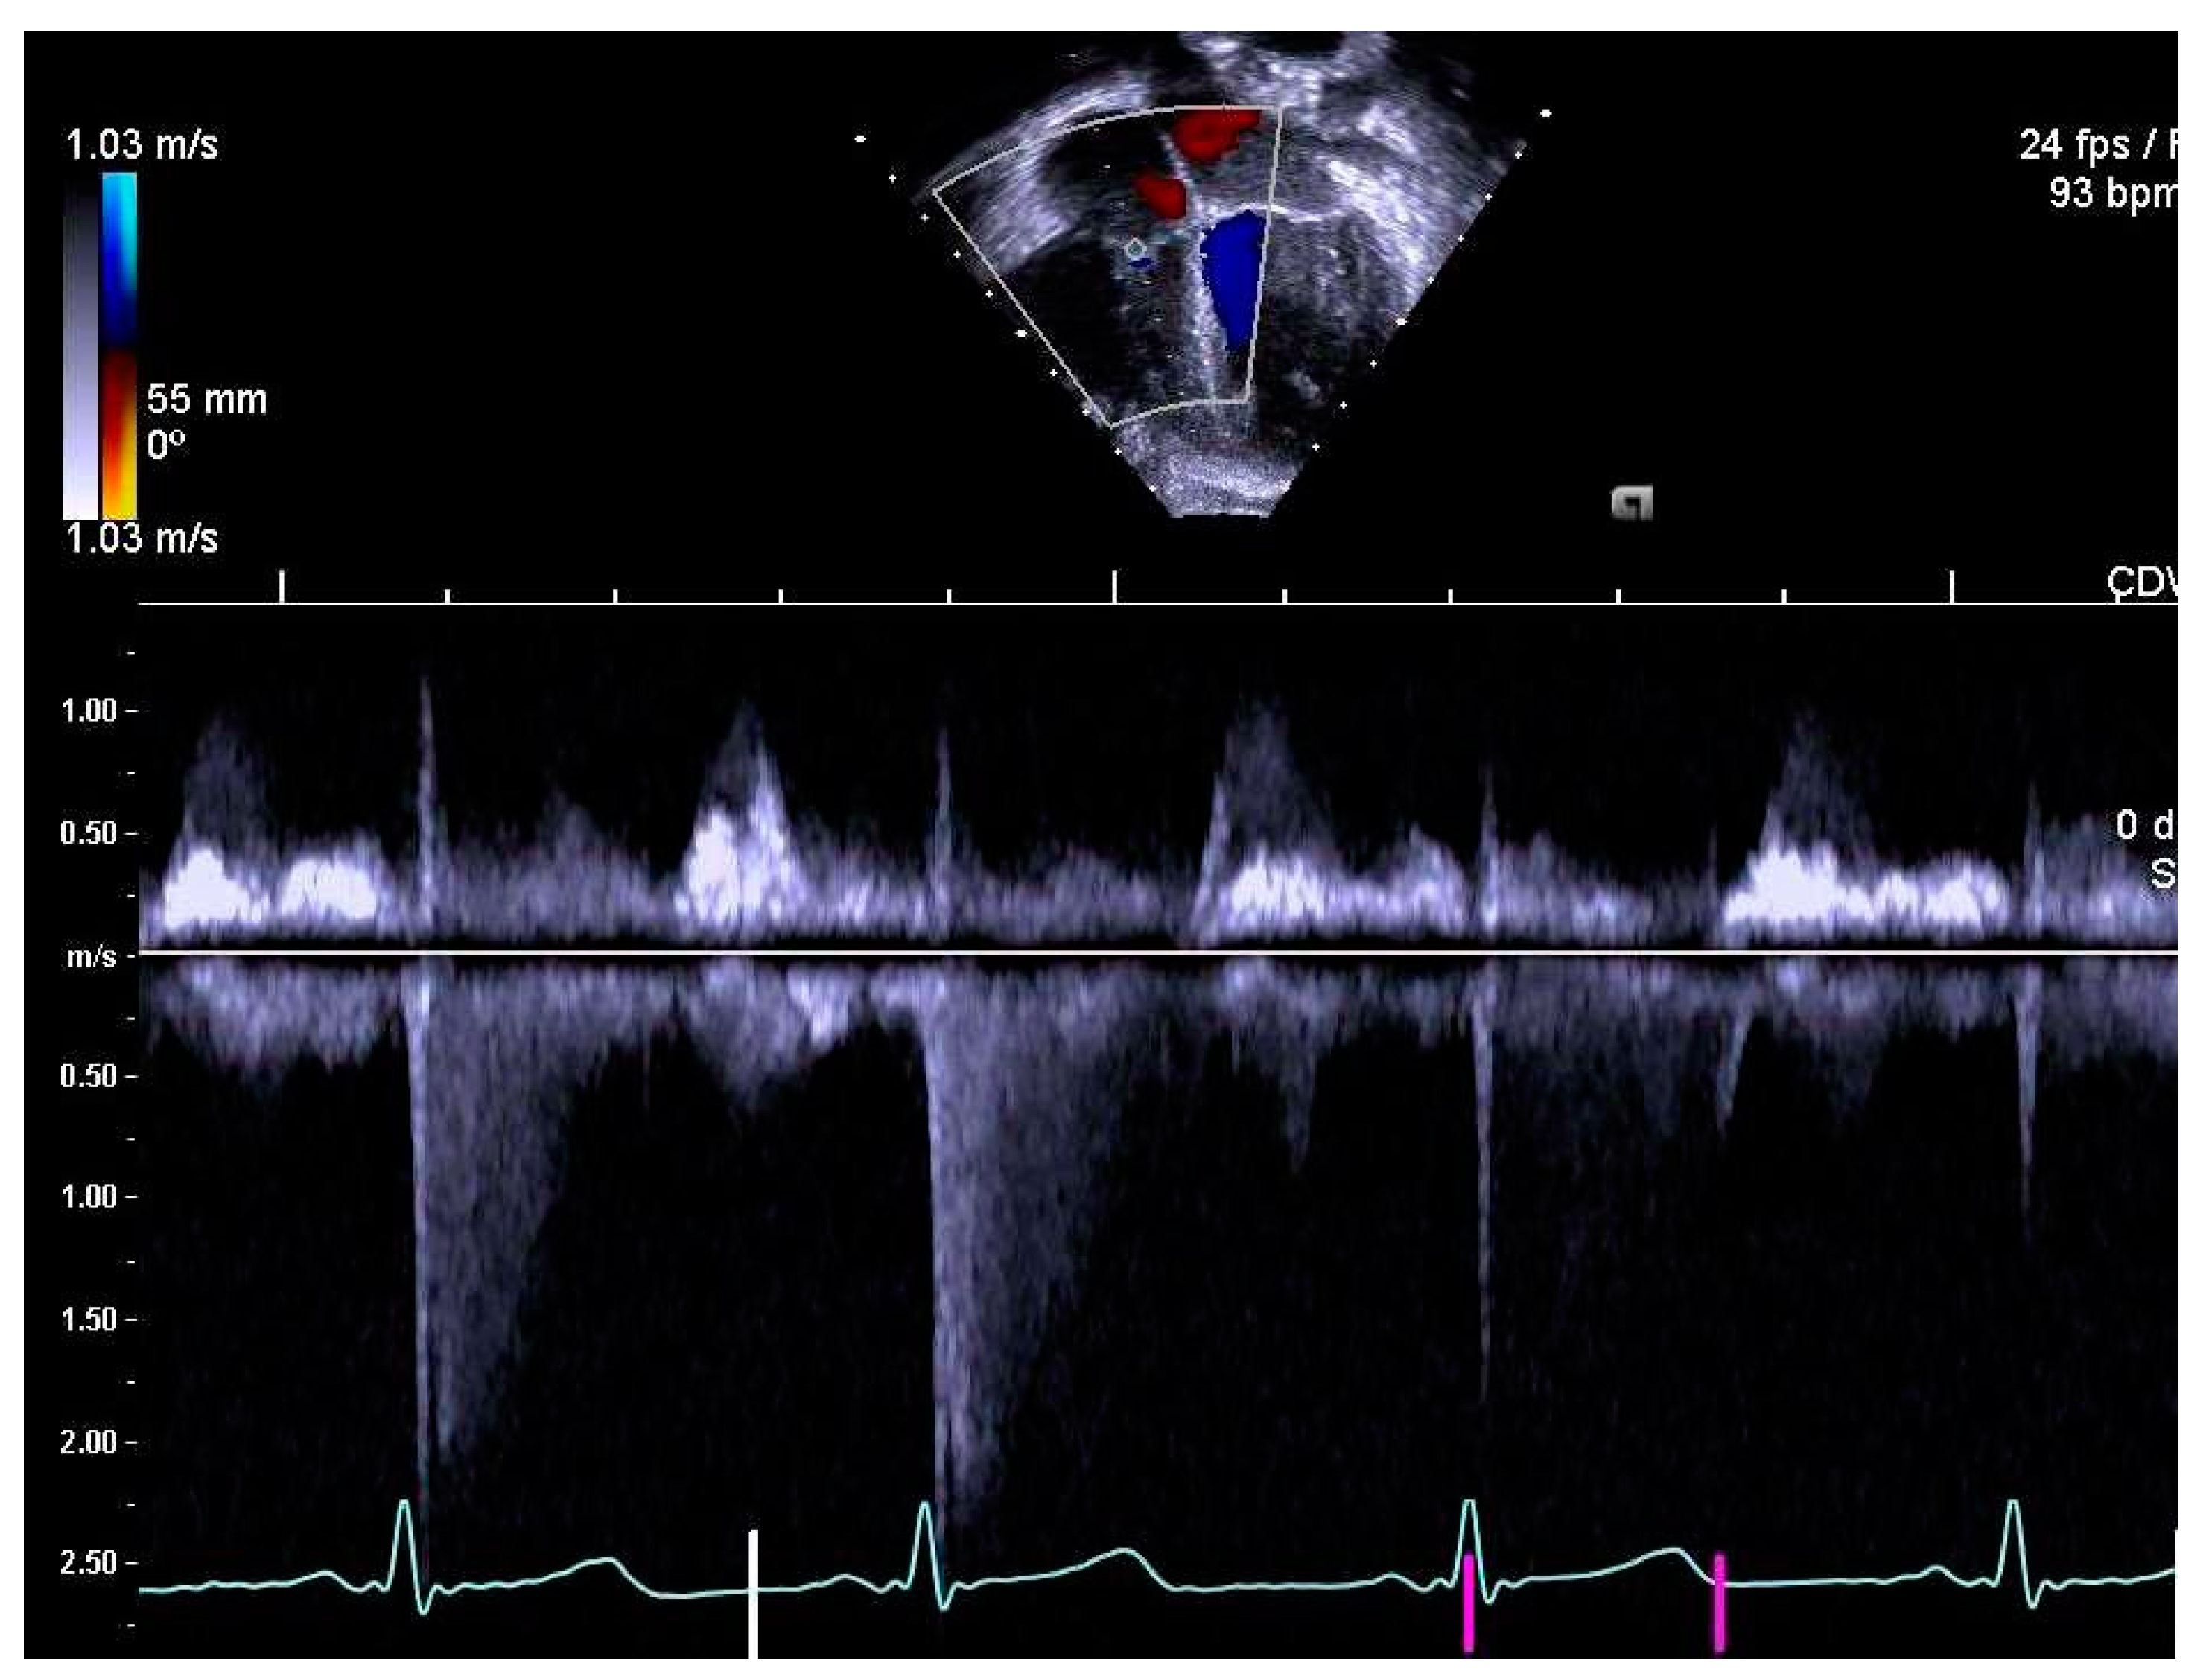

2.4. Determination of Right Heart Outcome Variables

3.5. Right Heart Systolic and Diastolic Functions

3.6. Perinatal Risk Factors and Right Heart Structure and Function in Children Born Extremely Preterm